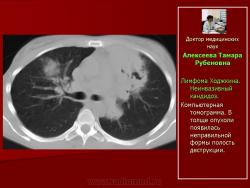

Рис.9.Б-ной С. Лимфома Ходжкина. Неинвазивный кандидоз.

Компьютерная томограмма. В толще опухоли появилась неправильной формы полость деструкции.